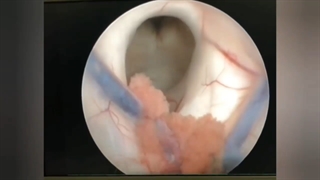

عمل جراحی آندوسکوپی آدنوم هیپوفیز که موجب بیماری کوشینگ میشود . بیماری کوشینگ به علت افزایش هورمون ترشح کننده غده هیپوفیز که منجر به افزایش شدید کورتیزول خون می شود به وجود می آید، بیمار دچار دیابت،فشار خون،پوکی استخوان و خطوط ارغوانی رنگ در پوست می شود. اطلاعات بیشتر : http://drsamadian.com